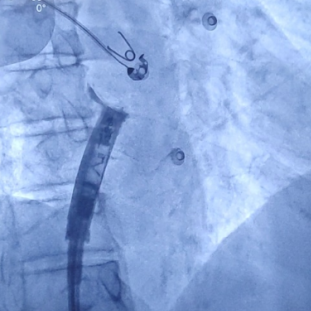

心房无导线起搏器最终植入位置

手术首先利用电生理四极导管标测Bachmann束区域,留影做参考;再次利用保护套筒造影精准确认植入位置,后退保护套筒,将心房无导线旋入1.5圈,参数良好且稳定。